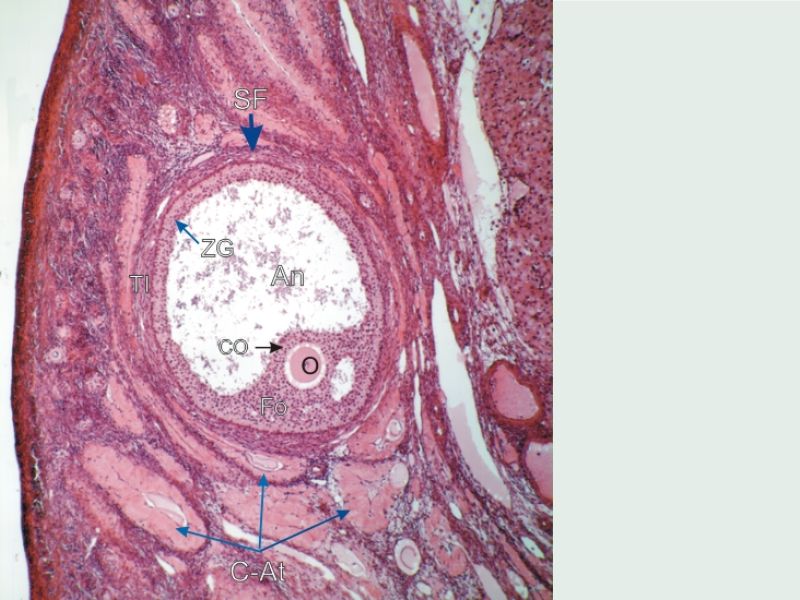

Follicular maturation

- Primordial follicle

- Growing follicle

- Primary follicle

- Secondary follicle

- Mature follicle (Graafian)

Components of a follicle

- Theca

- externa

- interna

- basal lamina

- Granulosa cells

- Antrum

- Cumulus oophorus >> Corona radiata

- Oocyte